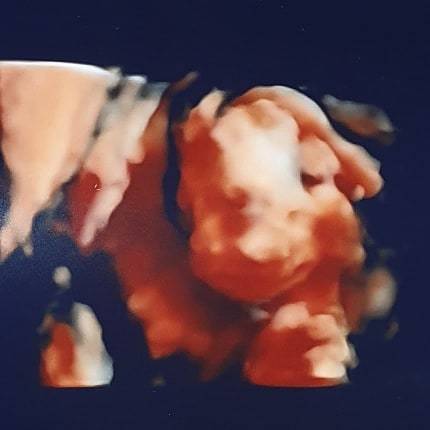

sao81 · 24/12/2019 12:06

Baby is healthy and happy, they think my placenta is low which is why I keep having episodes of bleeding, so going to have further scans to check if it moves

@sao81 That's such a good picture!! Exciting day for you tomorrow with the family reveal! Hopefully the further scans will identify the causes of the bleeding x